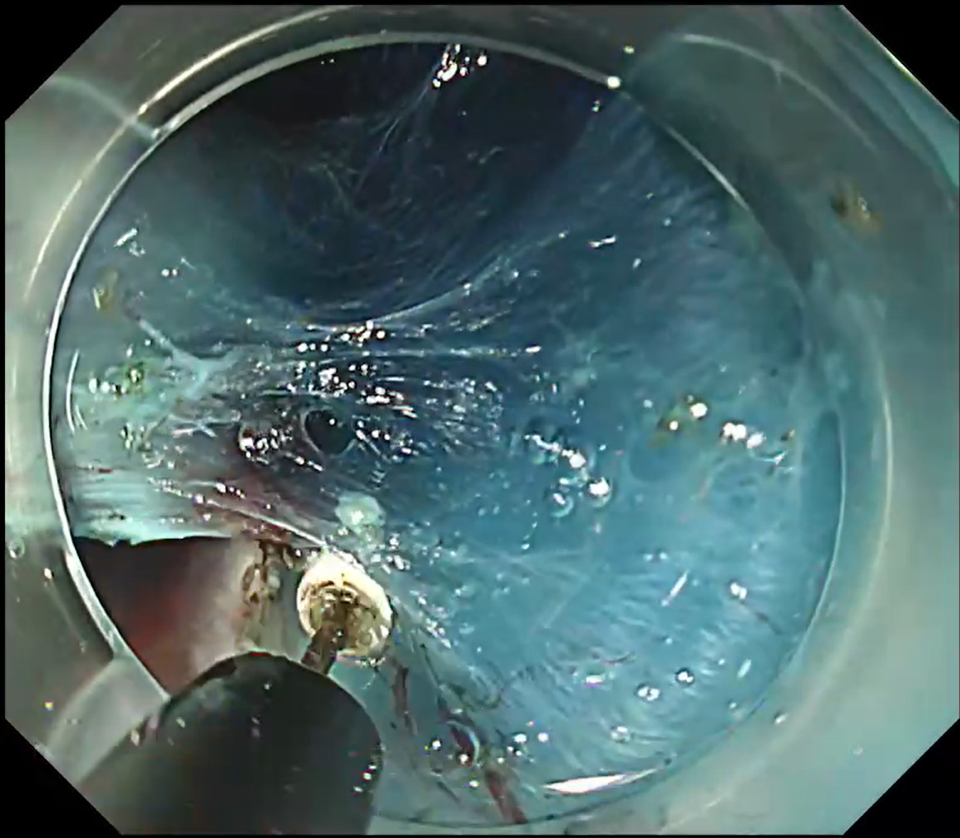

Once the flap was raised, clip-with-line traction was applied, and submucosal dissection was completed fairly quickly with the ITknife nano (Fig. 7, Movie 1). With traction in place, the theoretical risk of perforation approaches zero. Dissection is performed in coagulation mode, melting the tissue while keeping the white insulated back of the tip visible through the blue submucosa (Fig. 8).

Safety is enhanced by pushing the knife toward the lumen rather than pulling proximally.

Pull-cutting often slows the operator and leads to a shallow plane because of fear of damaging the muscle layer. Pushing the ITknife nano forward instead can produce surprisingly rapid

progress, the blunt tip tunnelling through the submucosa while maintaining a generous safety cushion.